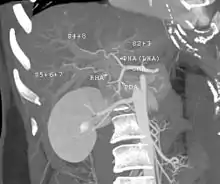

With the recent advances of noninvasive imaging, living liver donors usually have to undergo imaging examinations for liver anatomy to decide if the anatomy is feasible for donation. The evaluation is usually performed by multidetector row computed tomography (MDCT) and magnetic resonance imaging (MRI). MDCT is good in vascular anatomy and volumetry. MRI is used for biliary tree anatomy. Donors with very unusual vascular anatomy, which makes them unsuitable for donation, could be screened out to avoid unnecessary operations.

Shape of human liver in animation, with eight Couinaud segments labelled

In the widely used Couinaud system, the functional lobes are further divided into a total of eight subsegments based on a transverse plane through the bifurcation of the main portal vein.[28] The caudate lobe is a separate structure that receives blood flow from both the right- and left-sided vascular branches.[29][30] The Couinaud classification divides the liver into eight functionally independent liver segments. Each segment has its own vascular inflow, outflow and biliary drainage. In the centre of each segment are branches of the portal vein, hepatic artery, and bile duct. In the periphery of each segment is vascular outflow through the hepatic veins.[31] The classification system uses the vascular supply in the liver to separate the functional units (numbered I to VIII) with unit 1, the caudate lobe, receiving its supply from both the right and the left branches of the portal vein. It contains one or more hepatic veins which drain directly into the inferior vena cava.[28] The remainder of the units (II to VIII) are numbered in a clockwise fashion:[31]